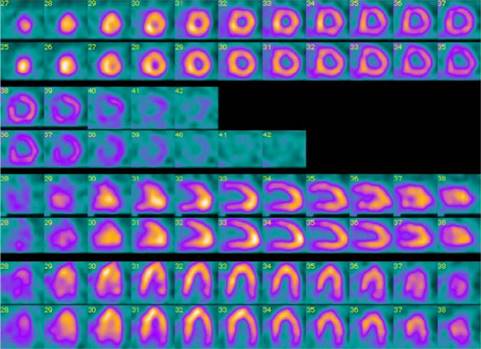

Paciente masculino en segunda década de la vida quien consulta al servicio de urgencia por cuadro clínico de 48 horas de evolución consistente en aumento del trabajo respiratorio e incremento de la clase funcional asociado a malestar general, fiebre no cuantificada y tendencia a la somnolencia con deterioro de los índices de oxigenación, por lo que se decide remitir a cuidados intensivos. Como único antecedente se refiere obesidad e hipertensión. Ingresa a la unidad de cuidados intensivos con tensión arterial de 60/30 mmHg, frecuencia respiratoria de 35 por minuto, frecuencia cardiaca de 150 latidos por minuto con registro en visoscopio sugestivo de fibrilación auricular, febril 39o con Glasgow de 10/15, saturación de 85% con Ventury al 50% con uso de músculos accesorios, por lo que se decide proteger vía aérea previa inducción de secuencia rápida con sedación y relajación, se realiza laringoscopia directa encontrando Cormack-Lehane III, se avanza tubo orotraqueal sin eventualidad1,2 monitoria de la ventilación mecánica, deterioro de propiedades pulmonares mecánicas dinámicas y estáticas con compliance en 28 cm de agua, presión meseta de 18 cm de agua, resistencias de la vía aérea en 6 cm3/litro/segundo, presión de conducción de 11 cm.3,4 Se accede vía central documentándose presiones de fin de lleno subóptimas con resistencias vasculares sistémicas en 450 dinas/superficie corporal/segundo. Información gasométrica con predicción aguda de bajo gasto por aumento del gradiente venoarterial de CO2 y predicción de hipoperfusión tisular por incremento del cociente metabólico anaeróbico, hiperlactatemia y acidemia metabólica importante.5,6 Se realiza electrocardiograma que documenta fibrilación auricular. Reportes de laboratorios de ingreso registrados en la Tabla 1. Se efectúan cultivos de vigilancia y se despliegan terapias tempranas dirigidas por objetivos.7,8 Es llevado a escanografía de tórax que documentan derrames pleurales bilaterales y consolidación más hepatización en el lóbulo medio (Figura 1). Se realiza ecocardiograma Doppler dúplex color transtorácico en virtud de hallazgos electrocardiográficos y marcadores de necrosis miocárdica referidos de ingreso, el cual reporta crecimiento del ventrículo izquierdo con fracción de eyección de 46% sin trastornos de la contractilidad, se descartó miocardiopatía inducida por sepsis con histonas negativas.9,10 Se decide estratificación de riesgo coronario con perfusión miocárdica isonitrilos, la cual revela miocardiopatía dilatada hibernante sin insuficiencia coronaria (Figura 2). Evoluciona con alto requerimiento de vasoactivos e inotrópicos con persistencia de falla circulatoria y marcadores de actividad inflamatoria en gases por hipercloremia e incremento de carboxihemoglobina, por lo que se decide escalamiento antibiótico.11 Presenta deterioro de la oxigenación y de la ventilación con deterioro de la mecánica ventilatoria, razón por la que se inicia protección pulmonar y ajuste de presión positiva por bucle presión volumen, meseta y fracción inspirada de oxígeno.12-14 Reportes de cultivos de vía aérea, hemocultivos y orina negativos; reporte de hisopado rectal documenta enterobacteria con resistencia extendida productora de muro péptidos e inductora de anhidromuropéptido codificado del gen C (AMPc), además mecanismos de resistencia nuclear por topoisomerasa IV y porción polirribosomal 50 s dando continuidad a carbapenémicos.15 Persiste fibrilación auricular e injuria pulmonar severa, por lo que se solicitan marcadores de actividad fibrinolítica con dímero D en 3.5 mg/dL. Es llevado a perfusión pulmonar documentándose defectos segmentarios de distribución vascular en los segmentos basales y laterales del lóbulo inferior izquierdo, así como segmento anterior del lóbulo superior ipsilateral y en segmento anterior del lóbulo superior derecho compatible con alta probabilidad de tromboembolismo pulmonar por criterios prospective investigative of study acute pulmonary embolism diagnosis (PISAPED) (Figura 3).16 Se documenta deficiencia de antitrombina III y mutación del factor V de Leiden en el escenario de estudios de hipercoagulabilidad y estudios autoinmunes negativos, los reportes se registran en la Tabla 2. Ante la persistencia de fibrilación auricular y choque obstructivo se decide trombólisis con lo cual se logra estabilidad hemodinámica y disminución en los parámetros ventilatorios. Evoluciona favorablemente con tolerancia a la suspensión del soporte farmacológico, se pasa a asa cerrada en asistencia proporcional con recuperación importante de la mecánica ventilatoria compliance total de 90 cm de agua, resistencias de 4 cm/litro/segundo, presión elástica alveolar de fin de espiración normal, elastancia de 20 cm de agua con trabajo respiratorio impuesto de 0.3 Jouls por litro, por lo que se realiza prueba única diaria con tubo en t sin predictores de falla de extubación, y se decide liberación de la ventilación mecánica.17,18 Es trasladado a piso para manejo por medicina interna y hematología.